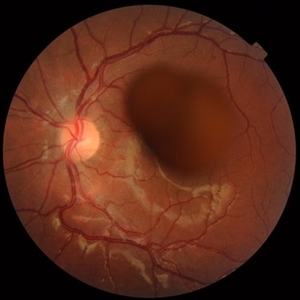

Best Disease Mar 9 2013 by Hamid Ahmadieh, MD Color fundus photograph the right eye of a 49-year-old man with decreased VA due to advanced Best disease. Photographer: Soodabeh Fooladin, Negah Eye Center, Tehran Condition/keywords: Best disease